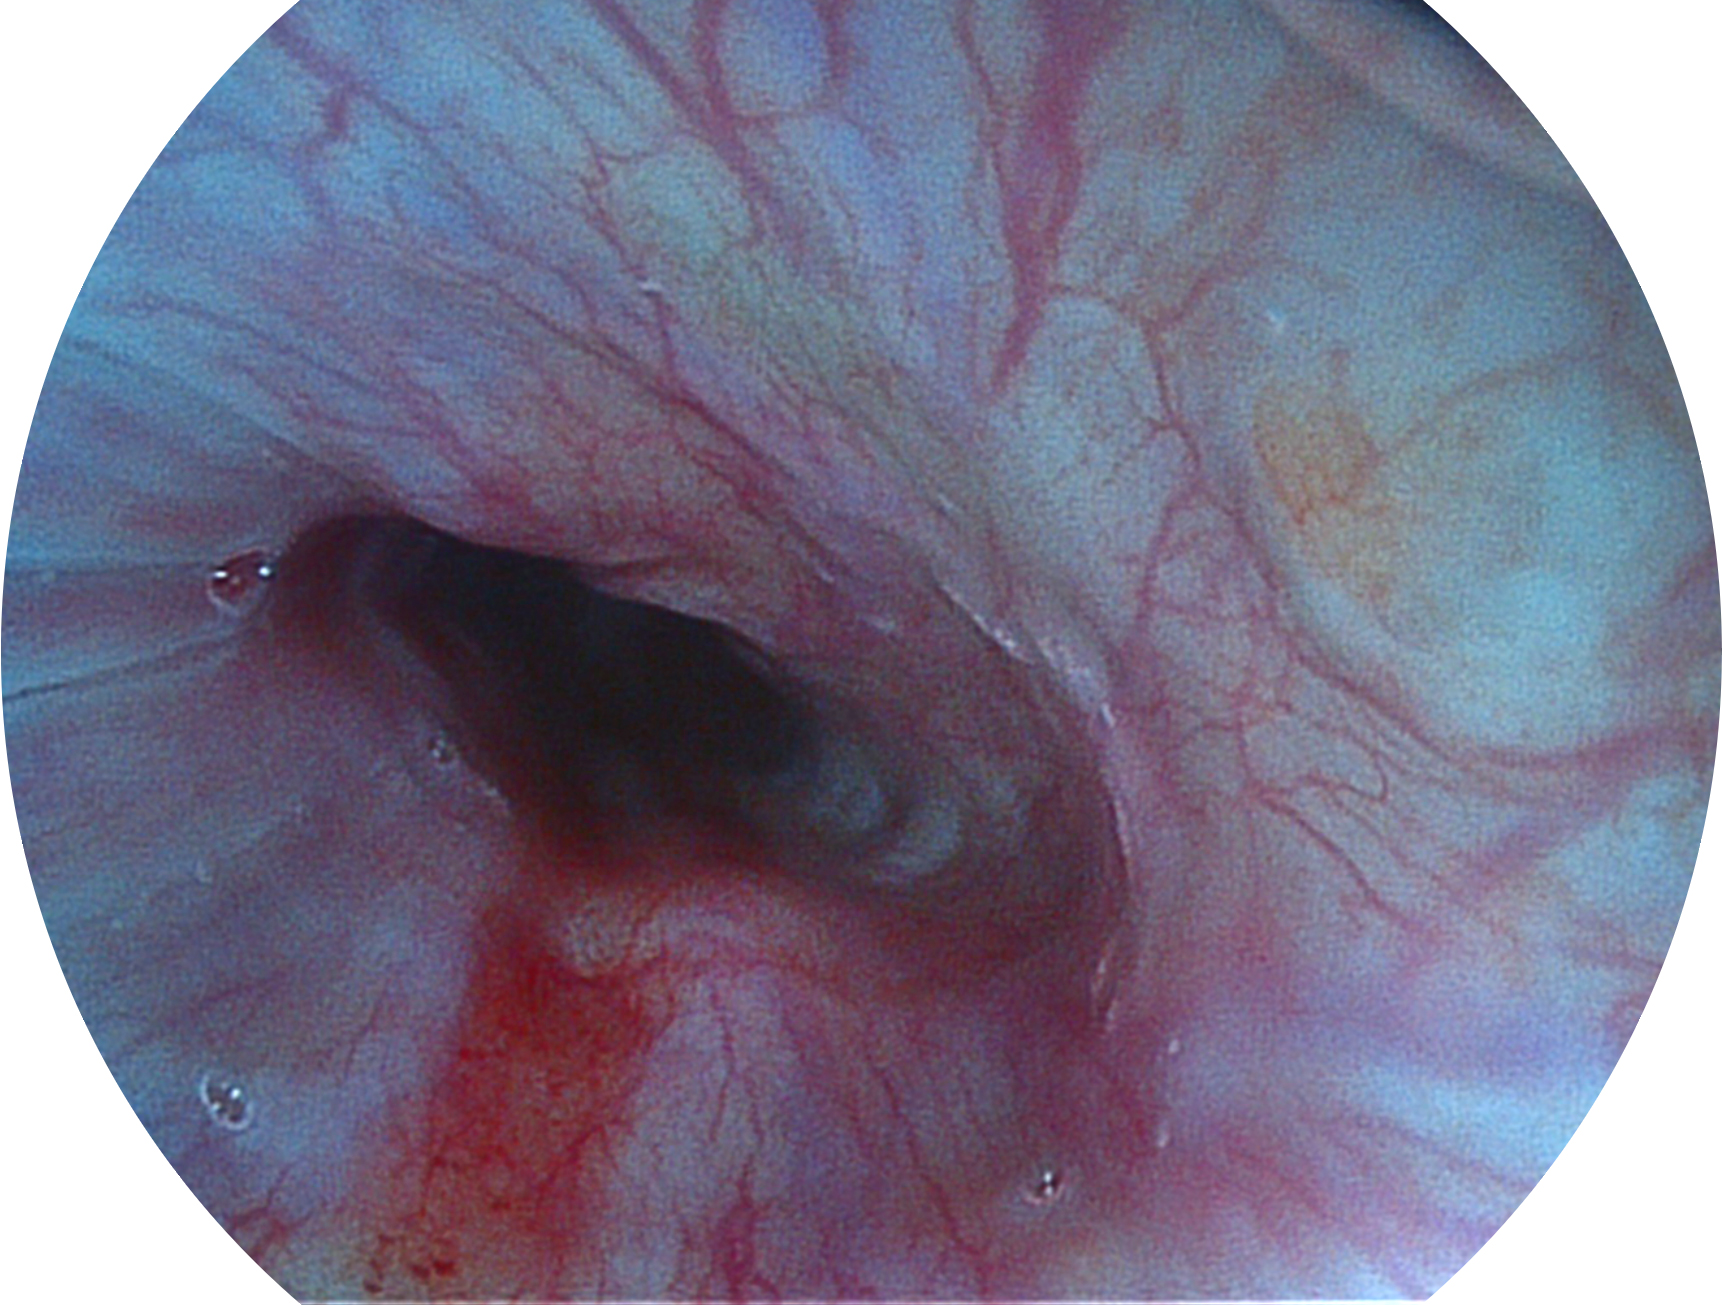

开立新开发的内镜染色技术,主要是基于多波长LED 光源的开发,VLS-55Q 四波长LED 光源是由四个不同颜色的LED光按照相应照明模式所规定的特定发光比例进行合束后形成,合束后形成的照明光的光谱由红光、绿光、蓝光及蓝紫光这四个不同的波段范围构成。具有更高光谱自由度,通过光谱比例的控制,实现了聚谱成像技术,英文全称为“Spectral Focused Imaging, SFI”,缩写为“SFI”和光电复合染色成像技术,英文全称为“Versatile Intelligent Staining Technology, VIST”,缩写为“VIST”。